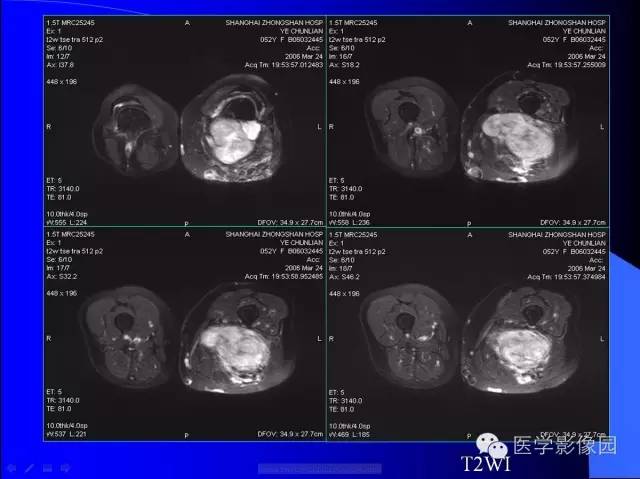

骨软骨瘤-恶变